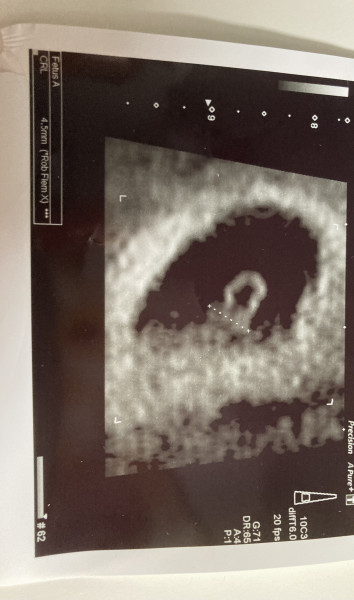

After immense tummy pain and the dreaded shoulder pain, I was utterly convinced this was ectopic. Turns out, everything is fine!

Lovely scan @DogsAndGin ! Welcome to the group @watermelonwizard :)

@DogsAndGin look at that little one go! It's worth feeling awful to see them safely where they are supposed to be. You must be so relieved! Congratulations.

@DogsAndGin thats amazing!! How far along are you? Lovely pic!!!!

@LC84 thank you 😊 I thought I was 6 weeks 6 days, but they reckon it’s more like 6 weeks. I couldn’t believe that everything was okay! I’d convinced myself it wasn’t going well 😅